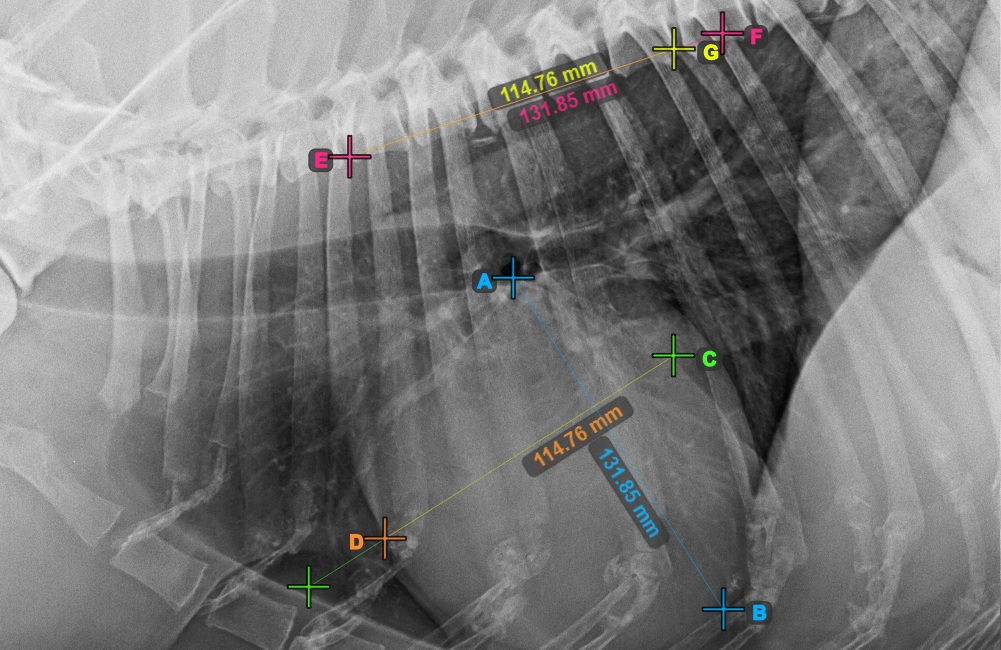

Identifizieren Sie den Beginn des T4-Wirbels (des vierten Wirbelkörpers der Wirbelsäule), ausgehend vom Anfangspunkt der Wirbelsäule. Markieren Sie den Beginn des T4-Wirbels, um die Messung fortzusetzen. Die Software zeichnet Linien vom markierten Punkt entlang der Wirbelsäule. Die Länge der Linien hängt von den gemessenen Längs- und Kurzachsen des Herzens ab.

Das Bild unten zeigt die typische Platzierung des Punkts am Beginn des vierten Wirbelkörpers der Wirbelsäule.

Bevor Sie mit den erforderlichen VHS-Berechnungen fortfahren, stellen Sie sicher, dass die Linien genau entlang der Wirbel platziert sind.

Zählen Sie die Anzahl der Wirbel entlang der Linie, die die Kurzachse der Wirbelsäule darstellt. Geben Sie die erforderliche Anzahl der Wirbel in das Eingabefeld Wirbelanzahl

in der Symbolleiste des erweiterten Messmodus ein.